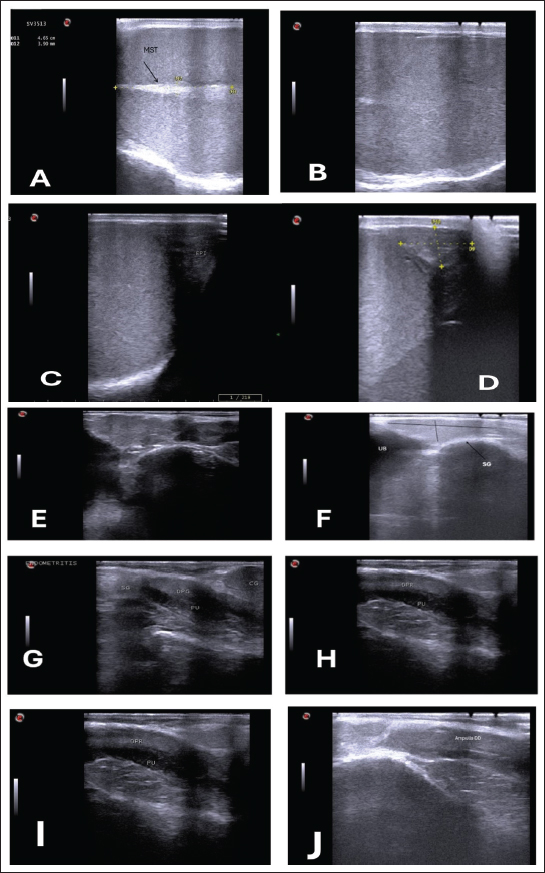

Fig. 1. (A) Parenchyma showing uniform echogenicity with large mediastinum tests (length and thickness) and homogenous appearance during the non-breeding season (B), (C) Show large size of epididymis compared to small size during nonbreeding season in(D). (E–H) Show different ecogenicity and variation in the size of male sex gland during breeding and non breeding season. (E) show enlargement and lobulation of seminal gland comparing to loss of lobulation and decrease in its size in (F). (I) also show more clear dorsal part of prostate gland during breeding season. The tail of the epididymis caught on from a slanting plane near the distal pole of the testis. Ultrasonographic scan of the testis showing the tail of the epididymis. The tail appears to be larger, heterogeneous in echotexture, and less echogenic than the testis, which may be related to distension with semen content during the mating season (Fig. 1C). During the non-breeding season, the tail of the epididymis is significantly smaller and more homogenous, indicating decreased sperm storage activity (Fig. 1D; Table 3). Table 3. Comparison of the epididymal tails of rams during and outside the breeding season.

The sex glands of the rats were evaluated ultrasonographically, and the results declared seasonal fluctuations. Higher secretory activity was reflected in the seminal gland by enhanced echogenicity, more lobulated appearance, and clearly defined margins (heterogenous appearance) throughout the breeding season (Fig. 1E; Table 4). Additionally, compared with the nonbreeding phase, the prostate and bulbourethral glands had a denser echotexture and were marginally more noticeable (Fig. 1G–J). The glands seemed smaller, less distinct, and had a more uniform and diminished echogenic pattern during the non-breeding season as a result of lower functional activity (Fig. 1F). Table 4. Seasonal variation in the echogenicity of the glands.